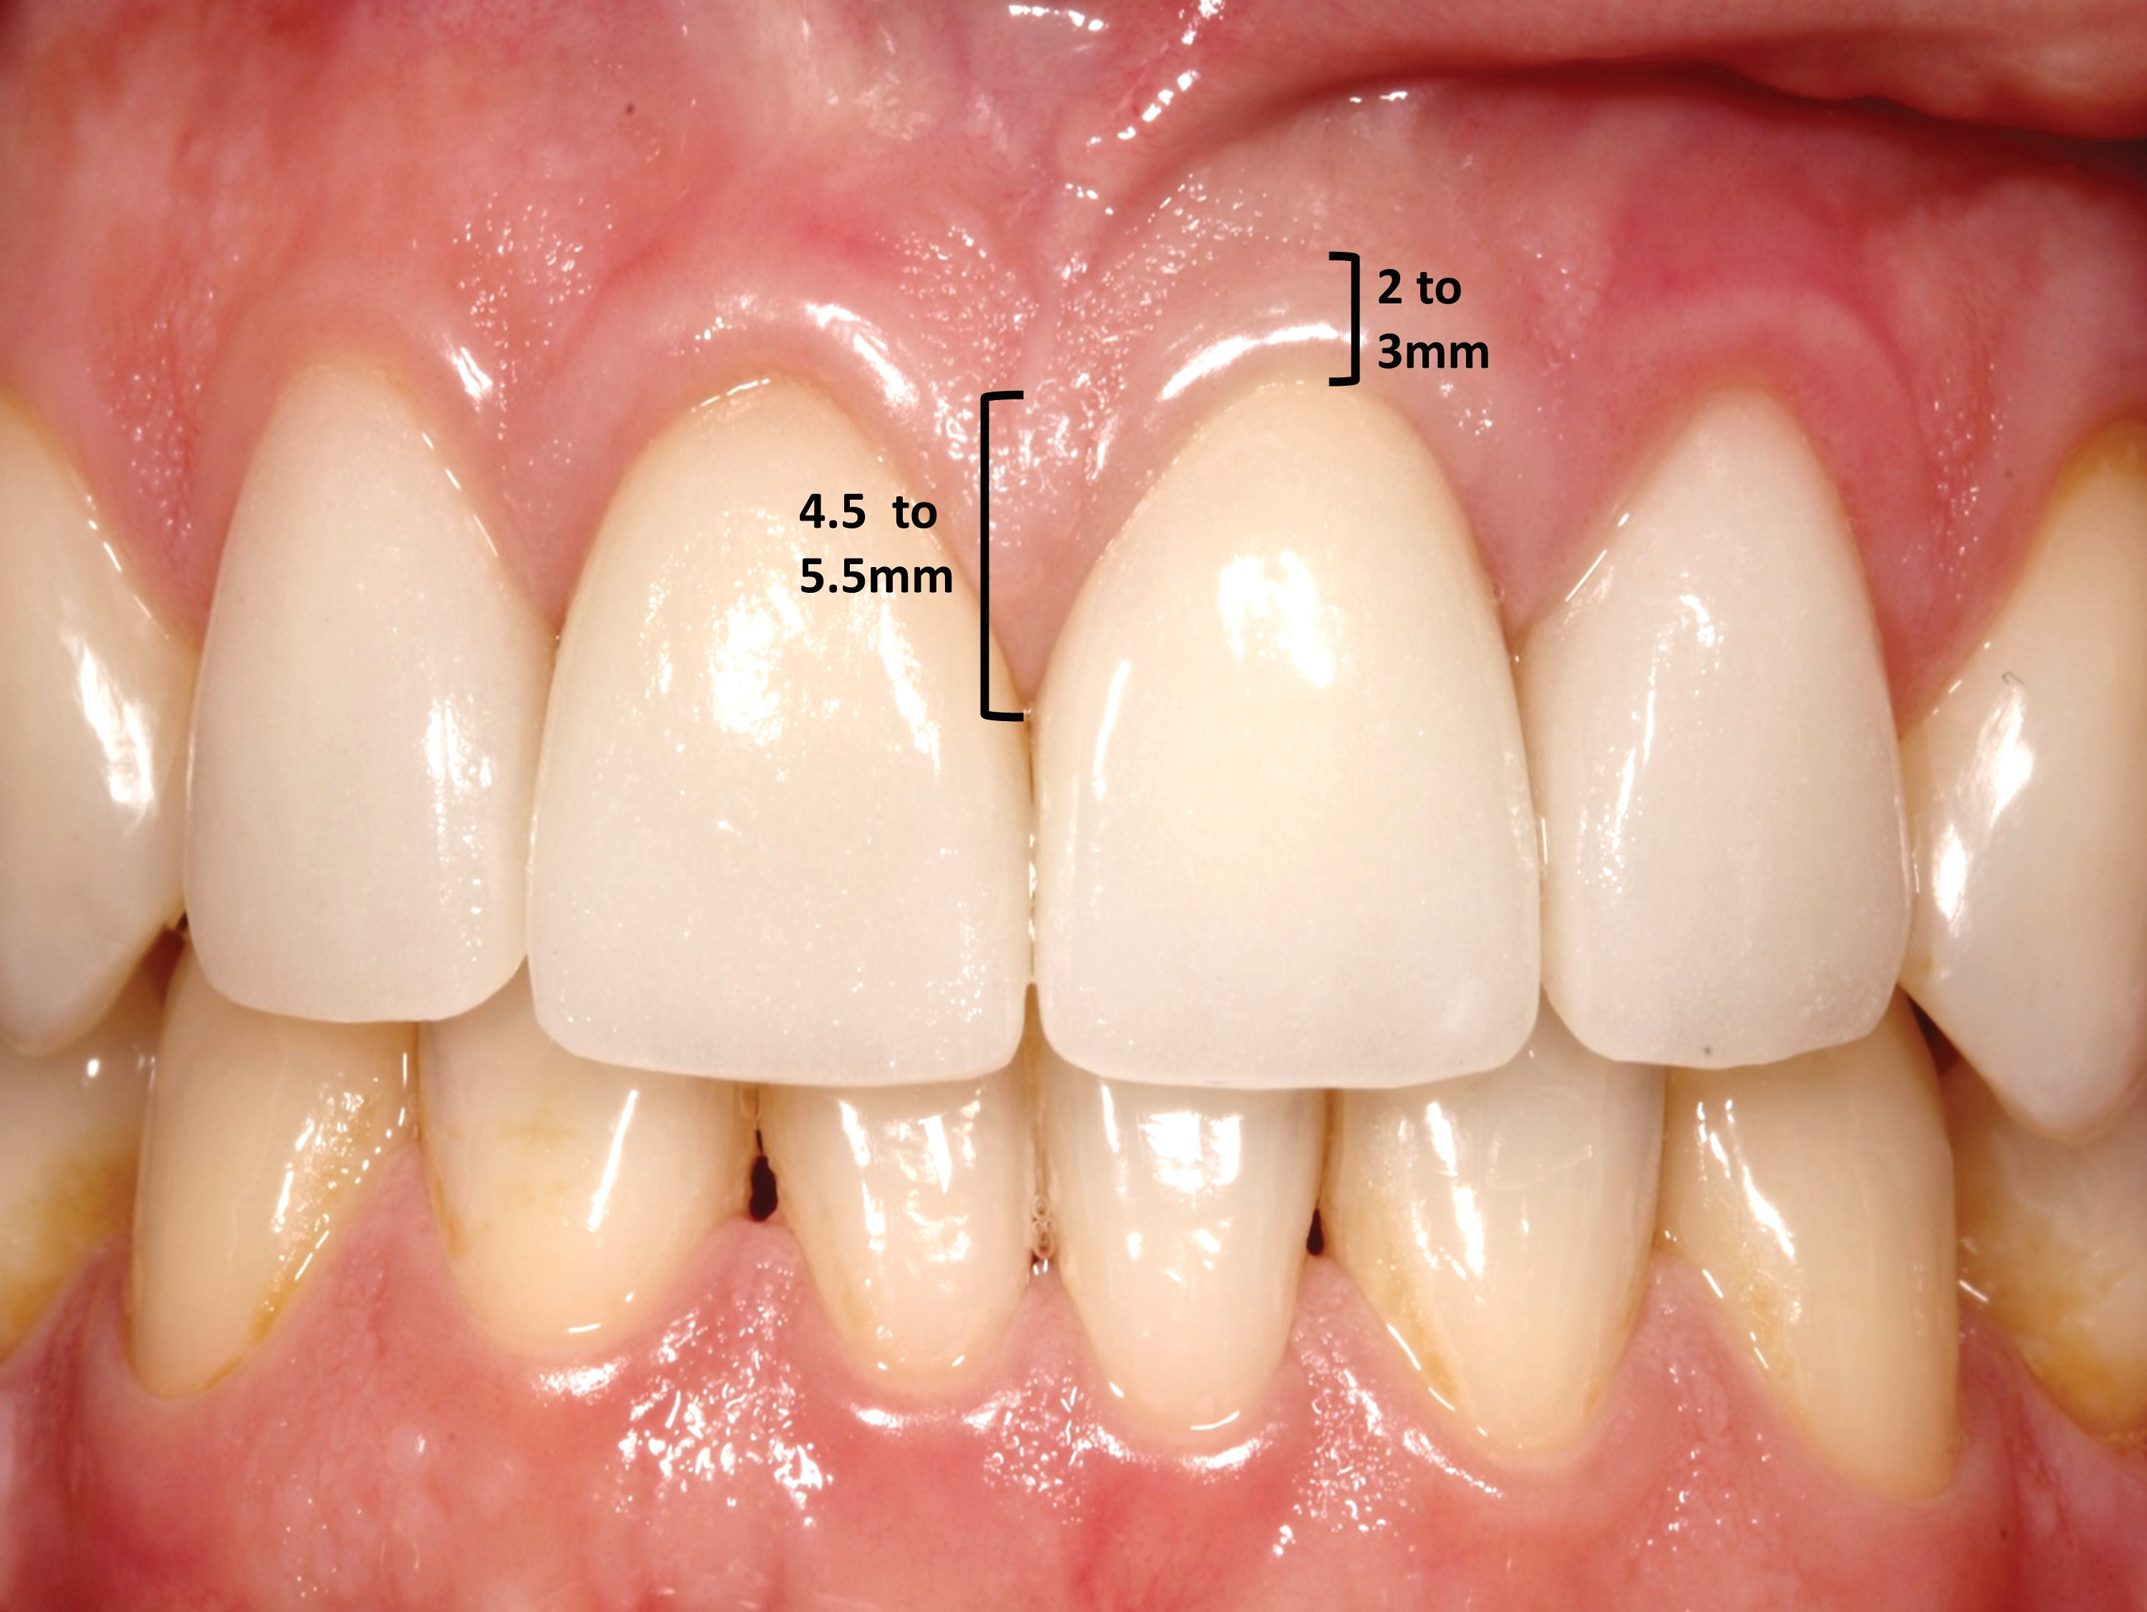

To facilitate treatment planning in the esthetic zone it is important for clinicians to know the dimensions of the gingiva, the osseous relationship with the overlying soft tissue, and the size of the teeth (Figure 1 and Figure 2) (Table 1).6

Fig 2. The buccal and lingual gingival level is located 2 mm to 3 mm coronal to the osseous crest. The interdental papilla between the central incisors is 4.5 mm to 5 mm coronal to the osseous crest. This is due to papillary hypertrophy.

Figure 2